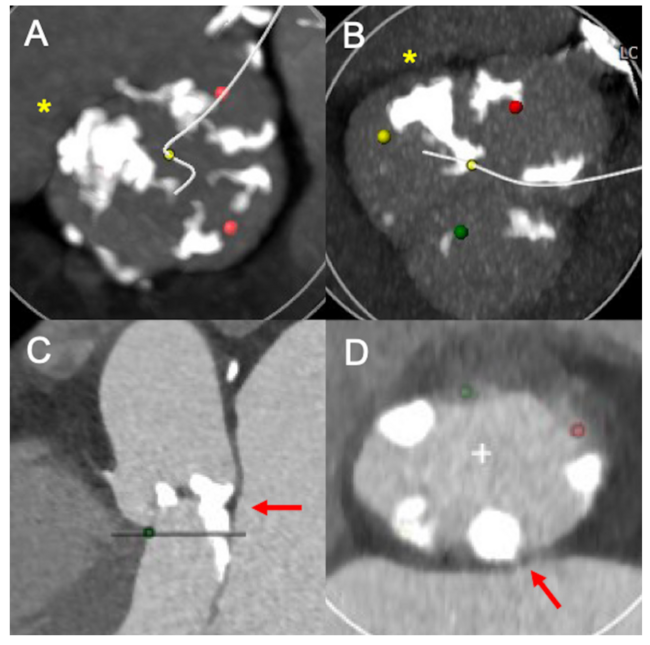

The aortic valve calcium score (AVCS) was measured according to the Agatston method using non-contrast-enhanced MDCT scans.9 The calcium density was calculated as AVCS/annular area (AU/cm2).10 The presence of eccentric aortic valve (AV) calcification and relevant left ventricular outflow tract (LVOT) calcification was determined by visual evaluation of the AV in short-axis views and maximum-intensity projections (Figure 1).11